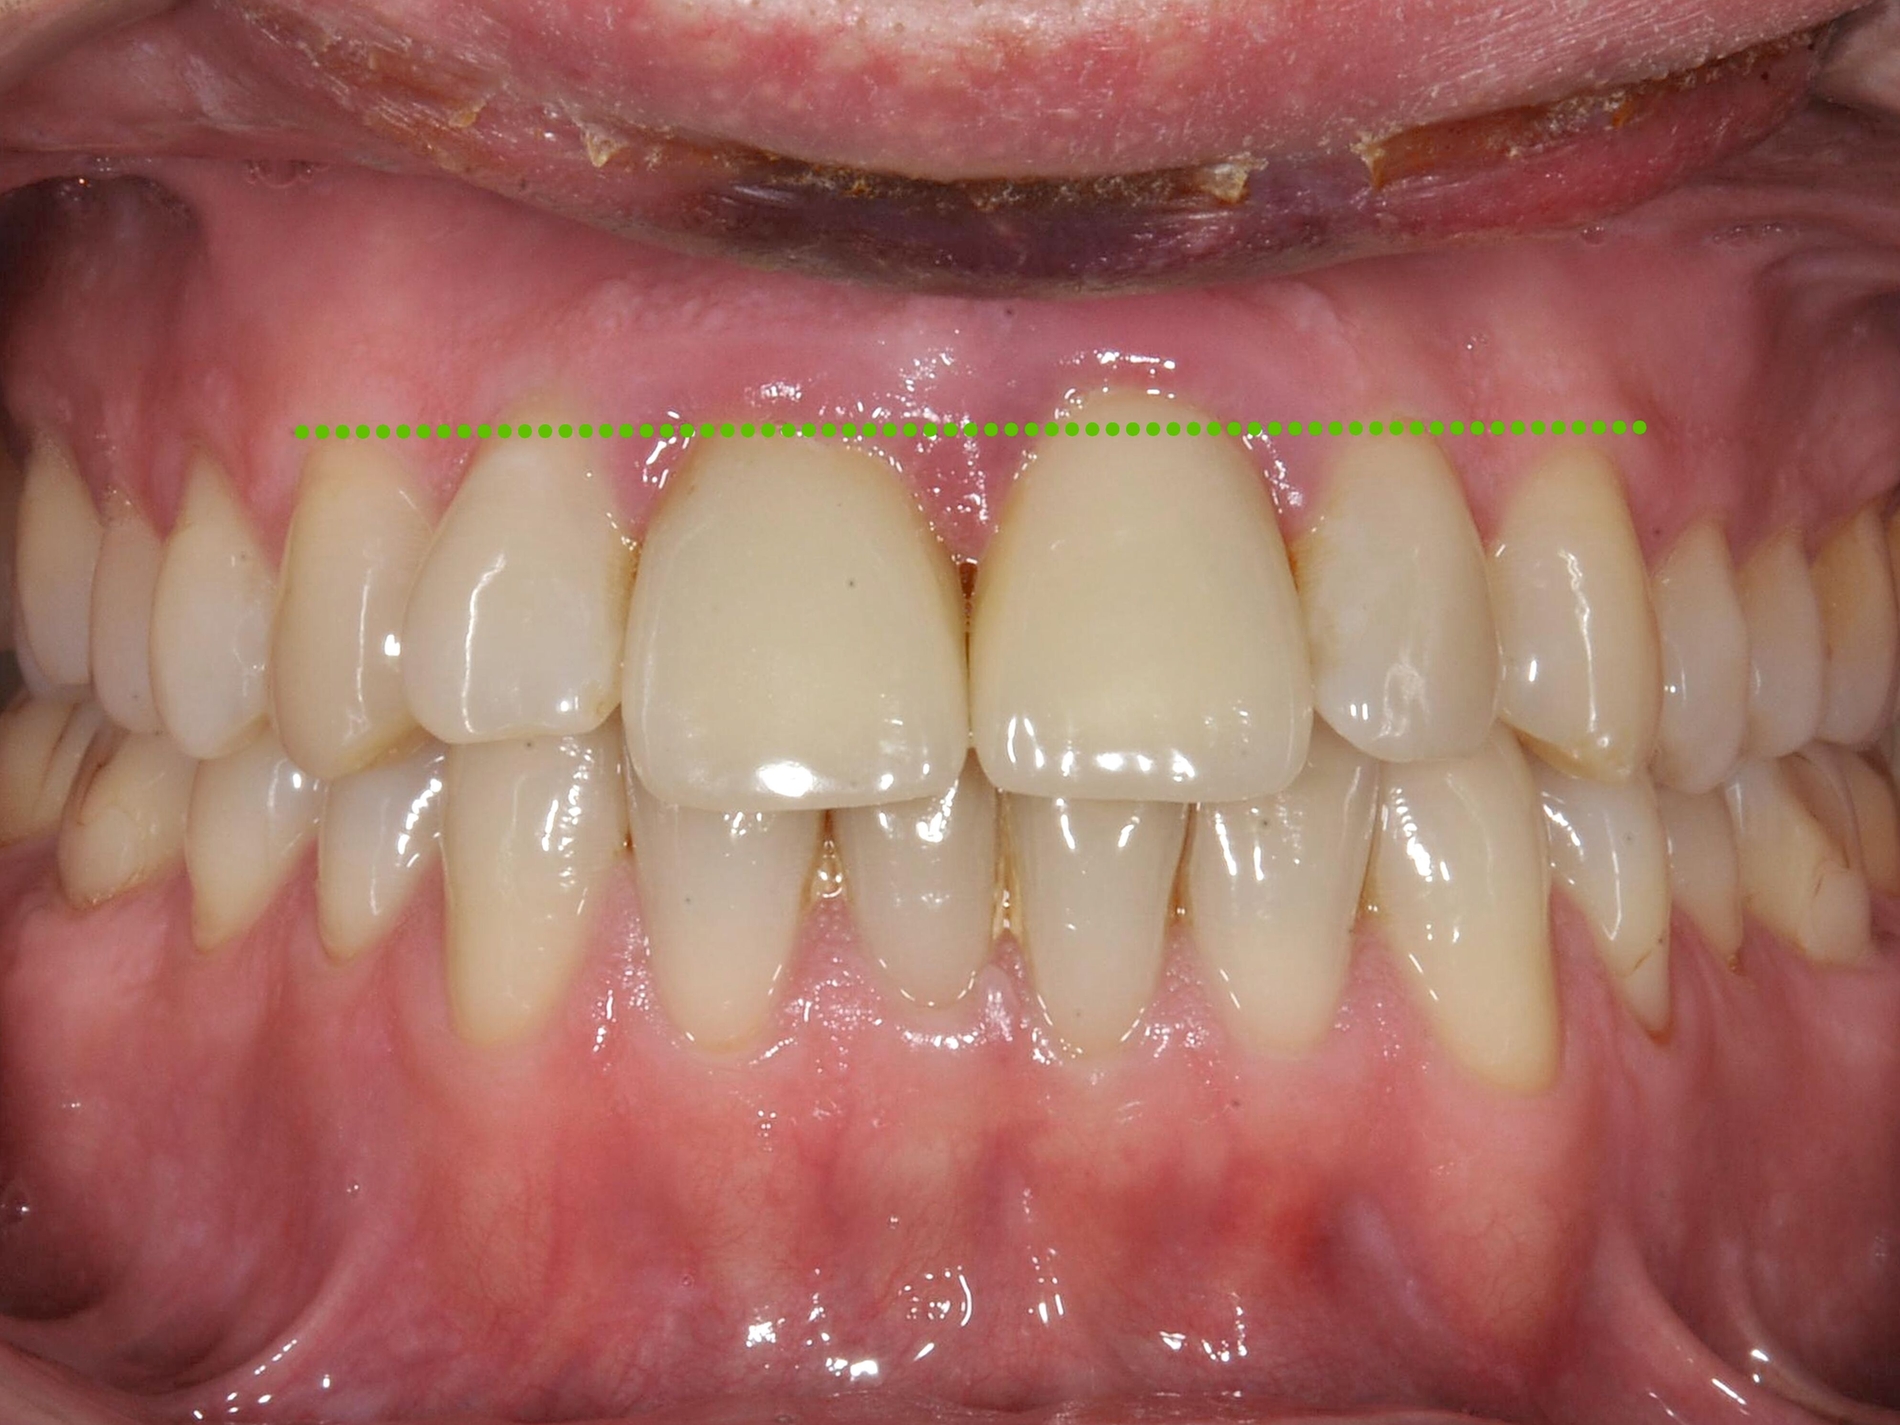

Eine Sonderform der kieferorthopädischen Extrusion ist die kieferorthopädische Extraktion, bei der die gesamte Wurzel langsam und kontrolliert aus der Alveole gehoben und am Ende extrahiert wird. Dieses Verfahren wird insbesondere dann angewendet, wenn ein Implantatbett mit ausreichendem Knochenangebot geschaffen werden soll [Bauer et al., 2019]. Schnelle und langsame Extrusionstechniken können jedoch auch bei einem Patienten kombiniert werden, wenn sowohl Anpassungen des Gingivaverlaufs als auch Veränderungen der Stumpfhöhe zur nachfolgenden Restauration geplant sind (Abbildung 2).

Schnelle kieferorthopädische Extrusionen im Sinne einer präprothetischen Maßnahme können zudem auch im Seitenzahnbereich indiziert sein, wenn für eine nachfolgende Kronenversorgung die notwendigen Voraussetzungen geschaffen werden sollen (ausreichende Stumpfhöhe, Einhaltung der biologischen Breite, Schaffung des Ferrule-Designs) [Gariulo et al., 1961; Juloski et al., 2012; Nugala et al., 2012] unter Einhalten eines Kronen-Wurzel-Verhältnisses von 1:1 [Grossmann und Sadan, 2005] (Abbildung 3).